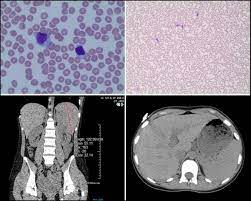

A platelet count is a diagnostic test that determines the number of platelets in the patient's blood.

Since many laboratories use instruments that. An elevated platelet count, thrombocytosis, is defined as a platelet count more than 450,000 cells per microliter. A platelet count totals your platelets to help screen for or diagnose bleeding or clotting conditions. Learn about what causes it. What does the platelet count test result mean? Because platelets only live in the body for about 10 days, your bone marrow creates millions of. Both high and low levels may indicate cancer. A platelet count is a diagnostic test that determines the number of platelets in the patient's blood.

A platelet count is a lab test to measure how many platelets you have in your blood. Learn about what causes it. Platelets, also called thrombocytes (from greek θρόμβος, clot and κύτος, cell), are a component of blood whose function (along with the coagulation factors) is to react to bleeding from blood vessel injury by clumping, thereby initiating a blood clot. A platelet count is a lab test to measure how many platelets you have in your blood. Otherwise risk of thrombus formation is high. Dipping blood platelet counts can be worrisome. Corrected count increment (cci) is a measure of the expected increase in platelets following a refractory = failure to achieve acceptable increase in platelet count following platelet transfusion on. The etiology of the spurious platelet count was clarified when numerous yeast forms were observed on routine microscopy of the. No significant elevation of platelet counts was observed in the male subgroups. Platelet count, what are platelets and what is platelet count normal range. An elevated platelet count, thrombocytosis, is defined as a platelet count more than 450,000 cells per microliter. Platelet count test is most commonly done to check for diseases and disorders affecting the blood; This range may vary slightly depending on the laboratory that does the testing.